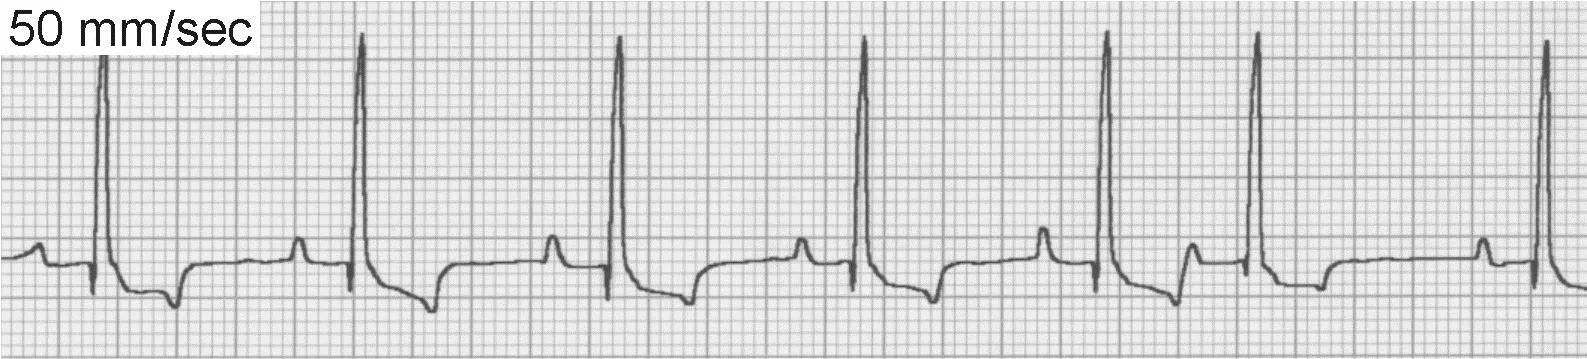

Supraventricular Premature Complexes

Underlying sinus rhythm with SV premature complexes will have QRS complexes that occur early (<1 R-R interval from the preceding sinus beat), maintain an SV morphology, and either lack P waves (junctional) or have P waves with aberrant morphology (atrial). SV premature complexes can be difficult to distinguish from sinus arrhythmia with a wandering pacemaker, although the former usually occurs at an instantaneous rate suggestive of tachycardia. The instantaneous rate is determined by counting the number of millimeters between 2 successive QRS complexes, and if recorded at 50 mm/sec, dividing that number into 3000.

SV premature complexes (Figure 6) are often produced subsequent to atrial enlargement associated with underlying myocardial, valvular, or congenital heart disease. SV premature complexes are occasionally seen in patients without clinical evidence of cardiac disease. The presence of these beats may precede development of further atrial arrhythmias, including SV tachycardia (SVT), atrial flutter, or atrial fibrillation.

FIGURE 6ECG of supraventricular premature complexes

In most cases, SV premature complexes are infrequent, do not cause clinical signs, and do not require treatment. In patients with paroxysms of SVT, treatment with digitalis, calcium-channel blockers, or β-blockers may be instituted. Treatment for underlying heart disease may also be necessary.